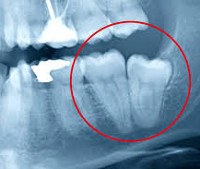

K03.5 Анкилоз зубов